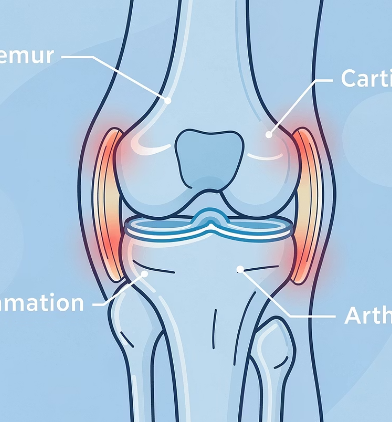

1. 퇴행성 관절염

중장년층에서 가장 흔한 원인입니다.

관절 연골이 닳으면서 염증이 생기고, 그 결과 관절액이 늘어나 무릎이 붓게 됩니다.

계단 오르내리기나 오래 걸을 때 통증이 동반되는 경우가 많습니다.

5. 류마티스 관절염

자가면역 질환으로 인해 관절에 만성 염증이 생깁니다.

양쪽 무릎이 동시에 붓는 경우가 많고, 아침에 뻣뻣함이 오래 지속됩니다.

단순 사용 과다와는 다른 양상을 보입니다.